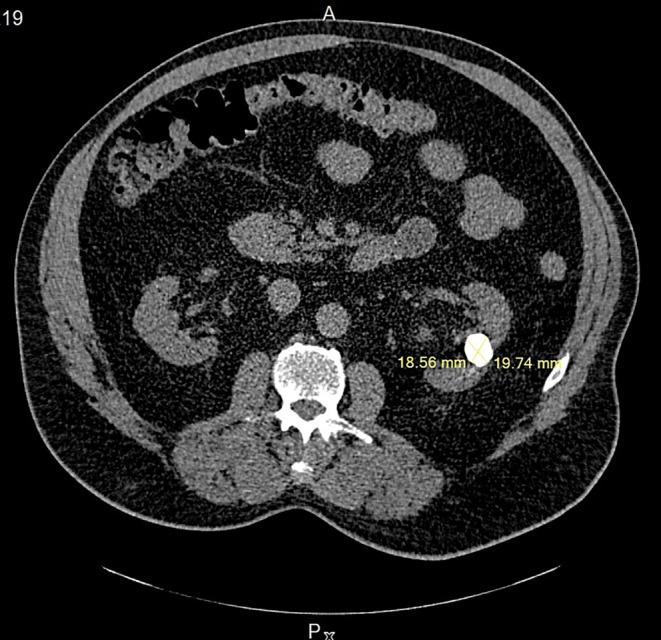

This study aims to present a case of laparoscopic nephrolithotomy and highlight its successful outcome. The patient was a 65-year-old male who experienced intermittent colicky flank pain. Imaging revealed the presence of a 20-mm round-shaped stone in a hydronephrotic calyx located in the mid-pole of the left kidney, possibly with a parenchymal component. Given the stone's location, neither percutaneous nephrolithotripsy (PCNL) nor ureterorenoscopy (URS) was considered feasible. The findings of this study demonstrate the effectiveness and suitability of laparoscopic nephrolithotomy (LNL) in managing stones. It emphasizes that LNL can be utilized not only as an alternative treatment but also as a viable initial option when appropriate case selection is made.

本研究旨在介绍一例腹腔镜肾切开取石术病例,并突出其成功结果。患者为一名65岁男性,经历间歇性绞痛性胁腹疼痛。影像学检查显示,在左肾中极肾积水的肾盏中有一个20毫米圆形结石,可能伴有实质成分。鉴于结石的位置,经皮肾镜取石术(PCNL)和输尿管肾镜检查(URS)均被认为不可行。本研究结果证明了腹腔镜肾切开取石术(LNL)在处理结石方面的有效性和适用性。它强调,当进行适当的病例选择时,LNL不仅可以作为一种替代治疗方法,而且可以作为一种可行的初始选择。